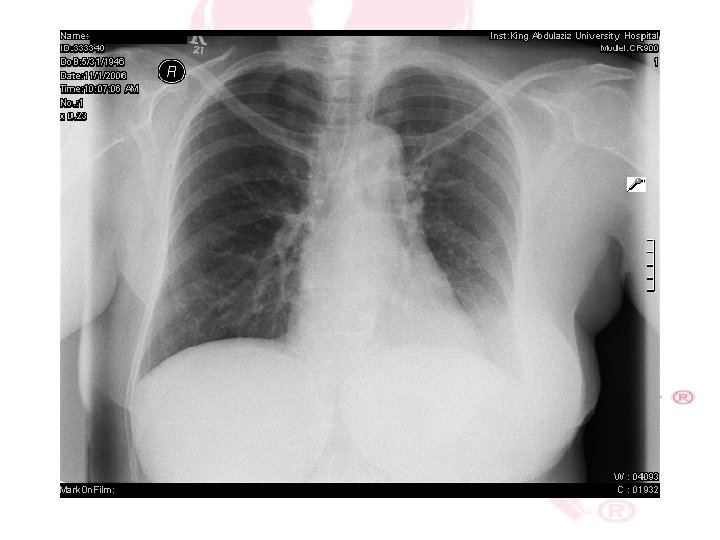

CHEST X-RAY